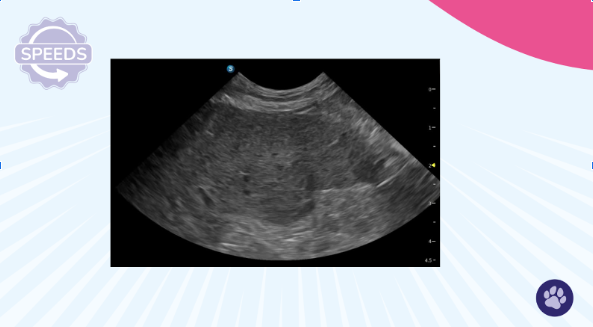

Ultrasound with colour Doppler showing normal hepatic blood flow

Dynamics: Blood Flow and Bile Flow

When thinking about dynamics in the liver, we're really thinking about blood flow and bile—how are these moving through the organ?

Normal Findings

You should see:

- Smooth portal veins with hyperechoic walls

- Unobstructed drainage via the caudal vena cava and hepatic veins

- No visible bile duct dilation (though in cats, small ducts might occasionally be seen and can be quite tortuous)